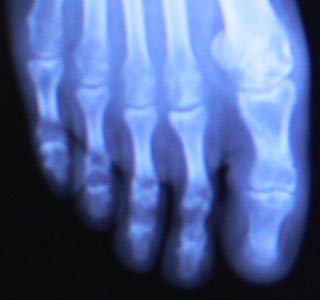

12月30日に撮ったレントゲン写真。

ピンは抜けていますが、まだ亀裂がわかりますね。

これからリハビリをしますが、決して無理をするな、と言われました。

急に体重をかけると、パキンと割れることがあるとのこと。